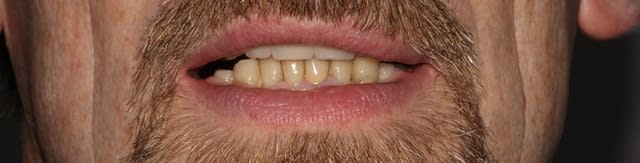

Allez, cas fini cette semaine, je vous le présente tel qu'il est arrivé.

-Pas de photo du visage pré-traitement, le patient ne sourie pas, probablement complexé, et je n'ai pas voulu en rajouter.

-La 23 est foutue, cariée jusqu'au trognon.